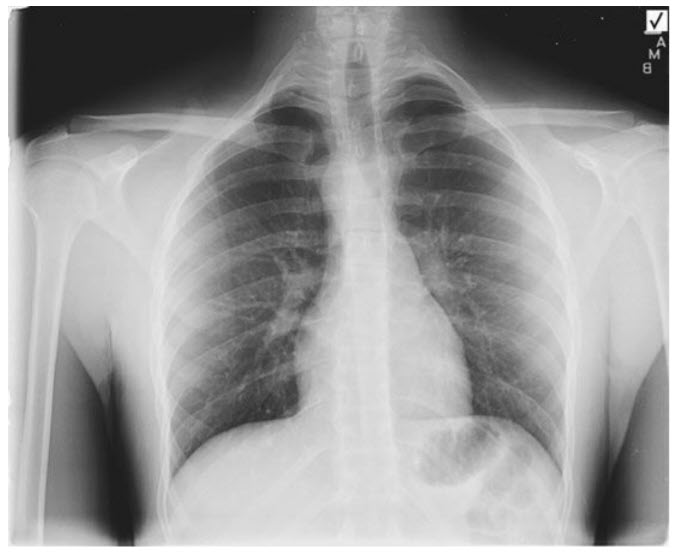

The CXR (Figure below) shows what abnormality?

Right-sided aortic arch. The CXR (Figure in question) shows a right-sided aortic arch with the aortic knob on the right side and absence of a left-sided aortic knob. A bovine aortic arch is an anatomic variant where the origin of the innominate artery and the left carotid artery arises from a common origin or the left carotid artery arises from the innominate artery. This variant occurs in approximately 13% of individuals and has no clinical significance. A cervical arch refers to the takeoff of the aortic branch vessels above the sternum into the soft tissues of the neck before turning downward to the descending aorta. It may present as a pulsatile mass in the neck or supraclavicular region and be associated with compressive symptoms and other vascular anomalies.

Tetralogy of Fallot. A right-sided aortic arch is most commonly associated with tetralogy of Fallot, particularly for the mirror image form. There are several types of right-sided aortic arch, but the mirror image and the nonmirror image variety are the most common. With the non-mirror image type, the order of branches from left to right are as follows: left carotid, right carotid, right subclavian, and left subclavian artery. The left (aberrant) subclavian artery arises from the descending aorta. The mirror image type is much more frequently associated with congenital anomalies than the nonmirror image type. Chest X-ray PA projection shows tracheal deviation to the left and round opacity on the right with absence of a distinct aortic knob on the left. This is most consistent with a right-sided arch (figure below).